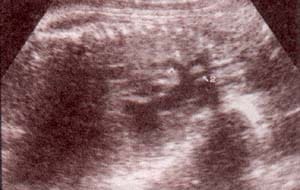

| fig 33.– (a). tractos de salida. 36 semanas. ventrículo derecho (1). arteria pulmonar (2). | fig. 33.-(b).ventrículo izquierdo (3). aorta (4). |

| fig 34. – (a).vasos intratorácicos. cayado aórtico (1). aorta descendente (2). vena cava (3). | fig. 34.– (b). cayado aórtico (1).vasos del cuello. carótida (2). |